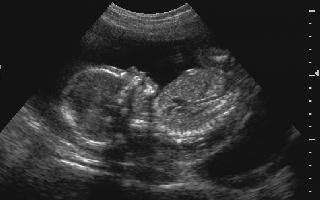

Can I video my OB sonogram?

Yes, with your phone after we confirm viability and fetal well being. We provide a thermal image if all is well.

Why do I need to fill my bladder with 32 oz. of fluid prior to my Obstetric/Pregnancy/Pelvic Sonogram?

Ultrasound transmits through fluid easier than tissue enabling improved resolution using the bladder as a "sonic window."

In pregnancy, it assists the sonographer by elevating the fetus, dorsi-flexing the lower uterine segment, which facilitates improved imaging of both the fetus and the cervix.

Is Ultrasound safe?

Ultrasound has been in use at its current level for over 30 years, and in that time no biological effects have been demonstrated. The Food and Drug Adminstration (FDA) also closely regulates the medical use of Diagnostic Ultrasound and will not allow a manufacturer to sell or import any systems for use in the United States that do not meet their criteria. The FDA criteria is very stringent as these systems perform on fetuses are more susceptible to heating and cavitation injury than are adults.